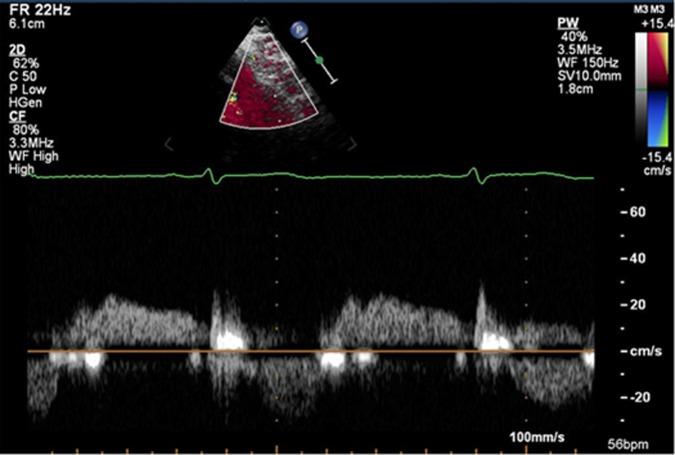

Takotsubo stress cardiomyopathy (TSC) is an increasingly recognised and diagnosed disease, although the underlying pathophysiology is still unknown. Our aim was to investigate the effect of the catecholamine dobutamine on coronary flow reserve (CFR) measured non-invasively in patients with TSC and controls. Our hypothesis was that dobutamine stress can induce microvascular dysfunction in patients with a previous episode of TSC.

This is a case-control study and a substudy of the Stockholm Myocardial Infarction with Normal Coronaries (SMINC) study. Elective dobutamine investigations were performed focusing on non-invasive measurements of CFR. The investigations were performed more than 6 months after the acute event.

CFR at low-dose dobutamine was significantly lower in the TSC group compared with controls, 1.51 and 1.72, respectively (p=0.017). At high-dose dobutamine, CFR was 1.95 and 2.21 in the TSC group and controls, respectively (p=0.098).

We could not confirm that the catecholamine dobutamine induced microvascular dysfunction in patients with TSC. However, we found a small but significant difference in CFR at low-dose dobutamine, which implies that the role of microvascular function in TSC needs to be further explored.